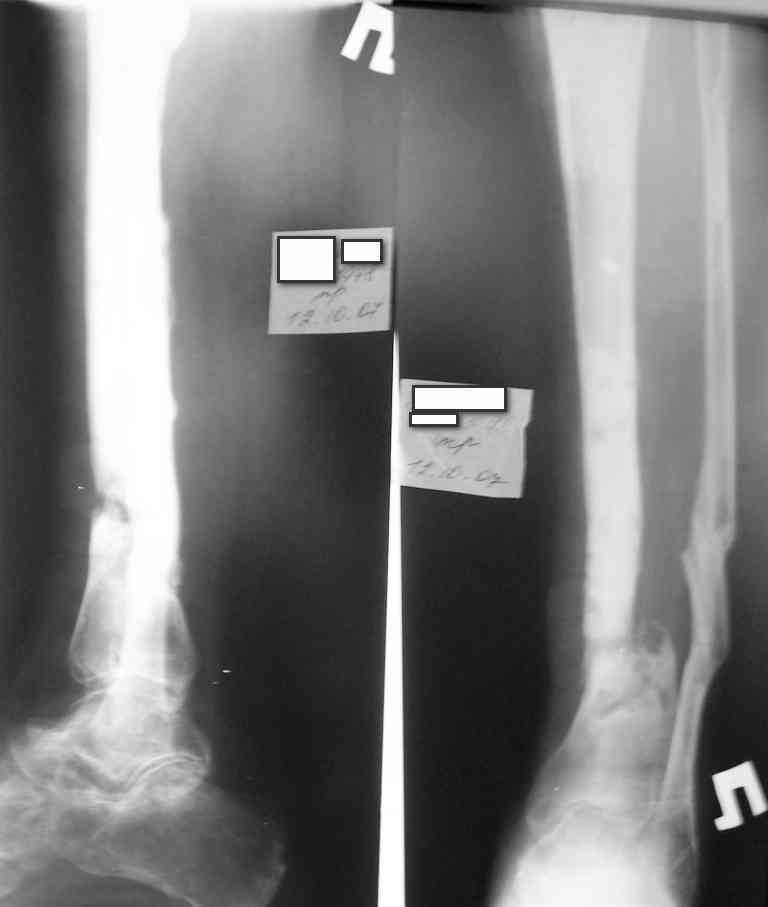

Инфицированное несращение tibia

Коротко анамнез: травма в 2004 г. - открытый оскольчатый перелом н/3 голени, имелась рана 4х5 см. по передне-внутренней поверхности. Заживление раны вторичным натяжением. Сращения в АВФ нет. В 2005 г. в нашей клинике произведена костная свободная аутопластика с наложением АВФ. В послеоперационном периоде некроз в области старого рубца 2х3 см., тогда же произведена кожная аутопластика на питающей ножке. Сращения в течение 6 мес. нет, аппарат снят.

В 2006 г. произведена костная аутопластика на сосудистой ножке, иммобилизация гипсовой повязкой. На данный момент признаков консолидации нет.

Периодически у пациента возникают явления дерматита на применение местно лекарственных препаратов на голени, периодически открывается точечный свищ по передней пповерхности в проекции ложного сустава с серозно-гнойным отделянмым.

Укорочение конечности на 4,5-5,0 см., растройств чувствительности нет. При ходьбе конечность нагружает практически полностью при использовании тутора и ортопедической обуви. Внешний вид и R-гр. на фото. У больного еще пока сохранился настрой на лечение.

У меня в мыслях в первую очередь удлинить конечность. В области ложного сустава вмешиваться страшно из-за плохой кожи. Какие будут мысли?